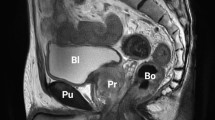

Definition of parameters in MRI measurements. (a) Axial section of MRI on T2 showing the maximum area of the prostate. A dashed-yellow line ‘BC’ indicates the maximum length of the width of the prostate at the section showing the maximum area of the prostate. The line is extended where it crosses the lateral edge of the obturator internus muscle. Point A and D were defined as the point crossing the lateral edge of the obturator internus muscle. ‘Prostate-muscle index (PMI)’ was defined as the sum of distance 'AB + CD' shown in a yellow line with arrowheads. (b) Sagittal section of MRI on T2 showing the pelvic cavity. ‘Anteroposterior diameter of the pelvic inlet (API)’, ‘pelvic depth (PD)’, and ‘anteroposterior diameter of the pelvic outlet (APO)’ were defined as the ‘diameter from the sacral promontory to the most superior aspect of the pubic symphysis’ (mm), ‘diameter from the sacral promontory to the most inferior point of the pubic symphysis’ (mm), ‘diameter from the inferior aspect of the pubic symphysis to the tip of the coccyx’ (mm). (c, d) Axial section of MRI onT2 showing the measurement of ISD and ASP. ‘Interspinous distance (ISD)’ was defined as ‘the narrowest distance between tips of the ischial spines’ (mm). ‘Angle of the symphysis pubis (ASP)’ was also measured. P: prostate, Fe: femoral bone, Pu: pubic bone, R: rectum, ObM: obturator internus muscle, Bl: bladder.

In this study, we used 4 known MRI-measurement parameters, namely PV, PCI, ASP, and APO. In addition, we proposed a novel parameter ‘PMI’, and compared its clinical performance and significance in the RARP procedure. PV was calculated by the ellipsoid formula, PV = width (cm) × length (cm) × height (cm) × (π/6)10. PCI was calculated by the following calculation formula, PCI = ‘anteroposterior diameter of the pelvic inlet’ (API: diameter from the sacral promontory to the most superior aspect of the pubic symphysis) (mm) × ‘interspinous distance’ (ISD) (mm) / ‘pelvic depth’ (PD: diameter from the sacral promontory to the most inferior point of the pubic symphysis) (mm) (Fig. 1b, c)7,11. ASP was measured as ‘the angle of the symphysis pubis’ (Fig. 1d) and APO was ‘diameter from the inferior aspect of the pubic symphysis to the tip of the coccyx’, respectively (Fig. 1b). PMI measurement was performed on the axial T2 weighted image section that showed the maximum width of the prostate. As shown in Fig. 1a, line BC shows the maximum length of the width of the prostate at the section showing the maximum area of the prostate and this line is extended to the point A and D, where the line BC crosses the lateral edge of the obturator internus muscle. The distance between AB and CD was measured and PMI was defined as the sum of distance 'AB + CD'. Therefore, PMI can be defined as ‘the distance between the inner edge of the obturator internus muscle and the lateral edge of the prostate at the MRI section showing the maximum width of the prostate’.